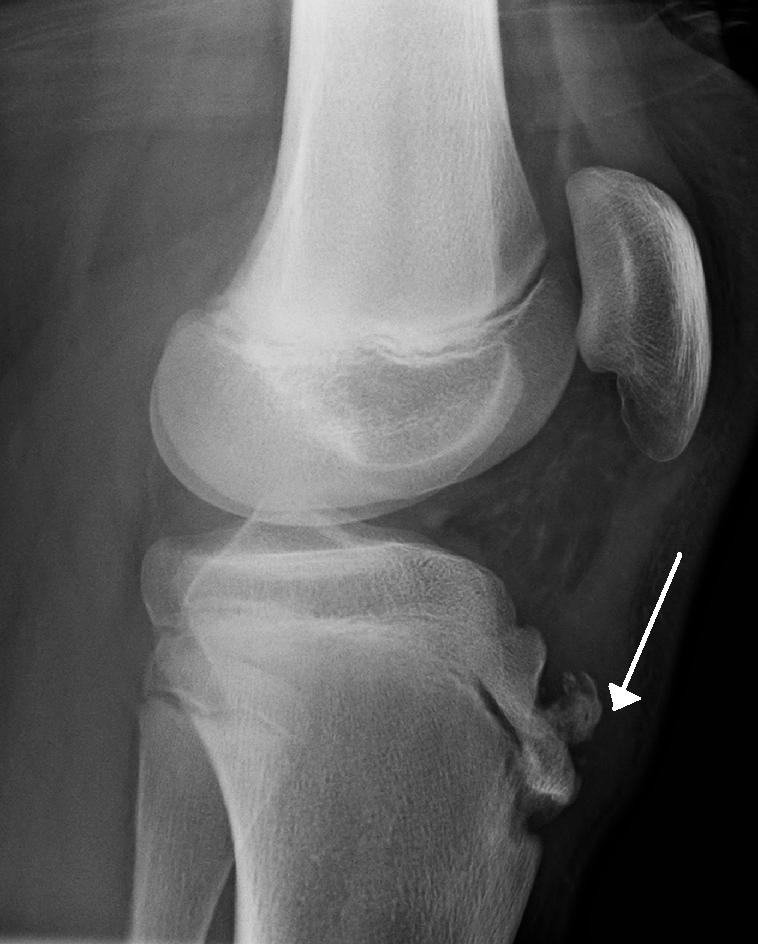

Knee with complete ACL rupture showing torn ligament, bone bruises on lateral femoral condyle and posterolateral...

Knee with medial meniscus tear (bucket-handle type) showing displaced meniscal fragment, joint effusion, and...

Degenerative knee with joint space narrowing, osteophytes, subchondral sclerosis, cartilage thinning, and Baker's cyst